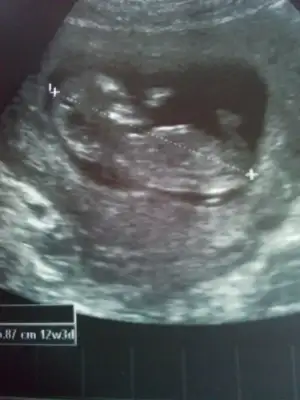

ikili test yaptırmıstım cuma gunu

1 hafta sonra sonuclarını alınca doktoruma göstercem

o zaman da belkı bı cınsıyet tamını yapar :D

Benimkide cok oynadi ama yinede soylemedi..anlamissindir sen dedik kemik yapisindan bile anlasiliyormus dedik ama yok oyle bisey su an deyince yaniltici oluyor dedi.:KK17:senin foto var mi canim.karsilatiririm en azindan.:KK47:

IMG_20150626_175645-1.webp IMG_20150626_180943-1.webp IMG_20150626_175849.webp